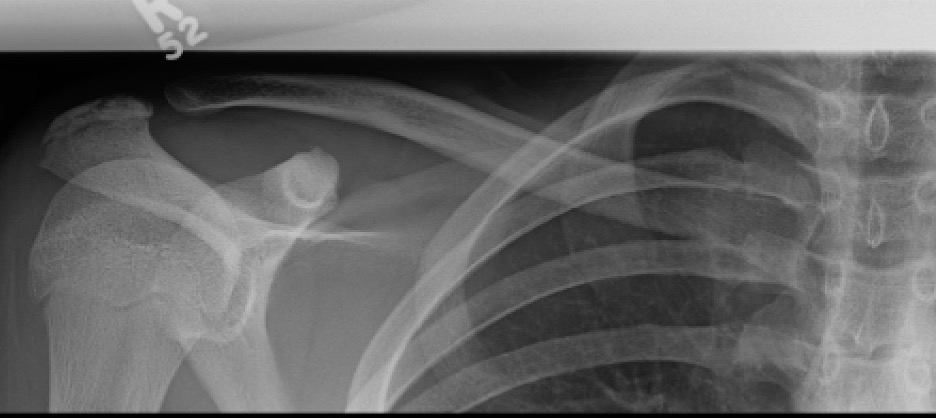

Xray

Can be missed on a xray

CT scan

Left posterior SCJ dislocation with pre- and post angiogram

Severe left posterior SCJ dislocation with subclavian vein compression